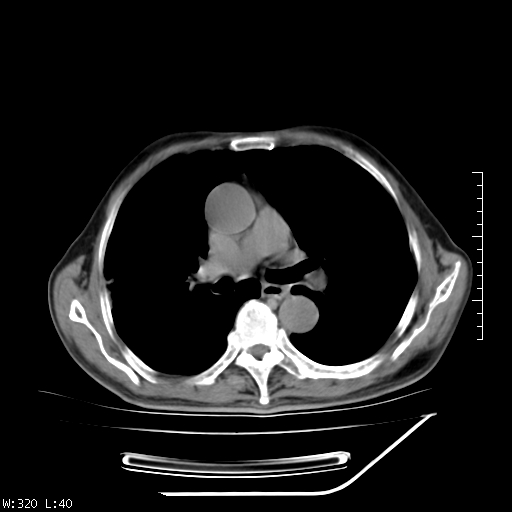

标题: CT23994:男、72、咳嗽、气短两月余,近来消瘦。 [打印本页]

标题: CT23994:男、72、咳嗽、气短两月余,近来消瘦。

右上肺实变,与胸膜关系密切,右肺容积缩小,隆突下淋巴结增大,考虑1 肺结核 2 肺癌

右上肺大片状密度增高影,与胸膜关系密切,内见低密度透亮影,胸膜下可见三角形不张影,左下肺沿支气管走形结节影,纵膈内淋巴结显示。考虑结核并疤痕性不张可能性大,建议穿刺活检,排除肺泡癌。